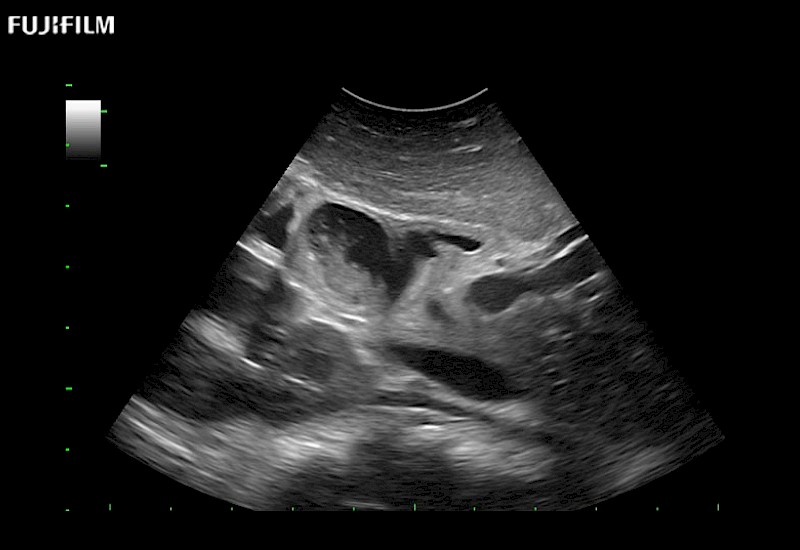

for use during general and laparoscopic procedures: Tumor localization & staging, Ablation, Resection, Biopsy, Transplant, Abdominal exploration, Robotic surgery

Our dedication to Laparoscopic Surgery allows us to offer superior image quality, outstanding system reliability and intuitive use of cutting edge technology.

Curved array 4-way laparoscopic transducer for better visualization of targeted lesions.

Main Specifications: